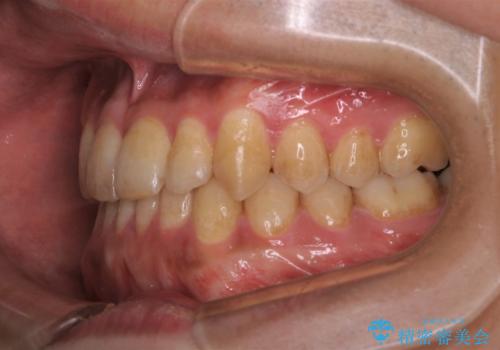

- 矯正治療が終わったので歯のクリーニングを希望され来院しました。

PMTC60分コースを行いました。

全体の歯の面に着色がついていました。PMTCを定期的に行うことにより、毎日の歯磨きやお食事によって傷ついた歯をツヤツヤでなめらかな歯にしてくれます。ですので着色が付着しにくい歯にすることができます。